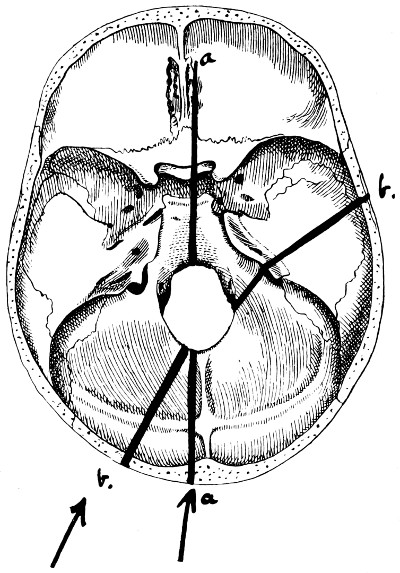

| 28. Illustrating the lines along which forces received on the vault are transmitted to the base | 69 |

| 29 A and B. The base of the skull and the base as seen on transillumination | 70, 71 |